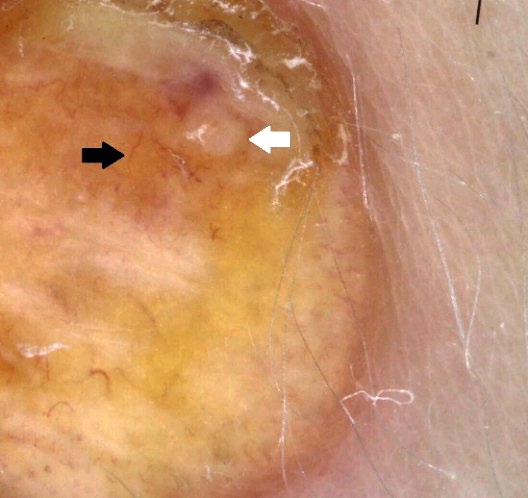

При дерматоскопии наблюдаются характерная дольчатая структура гиперплазированных сальных желез с расположением сосудов вокруг каждой дольки (crown vessels), нежная сосочковая папилломатозная поверхность и отсутствие волос, что патогномонично для невуса сальных желез (рис. 3).

Рис. 3. Дерматоскопия. Наблюдаются характерная дольчатая структура гиперплазированных сальных желез (белая стрелка) с расположением сосудов вокруг каждой дольки (crown vessels) (черная стрелка), нежная сосочковая папилломатозная поверхность и отсутствие волос